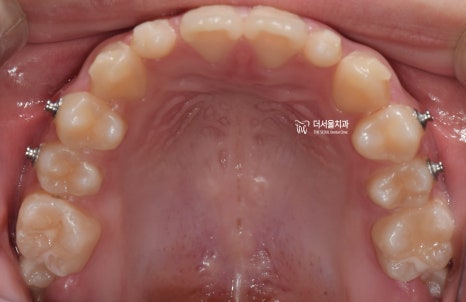

『구강 내 사진』

성장교정 이 필요한 이유는,

구강 내 사진에서도 뚜렷히 찾아볼 수 있습니다.

유치가 빠지면서 영구치아가 올라오고 있는

혼합치열기에서, 영구치가 올라올 수 있는

충분한 공간을 확보하면서

턱의 위치를 바로 잡는것이 핵심포인트입니다.

우선 여기서 봐야 될 큰 문제는

1) 절단교합(Edge to edge bite) 입니다.

윗니가 아랫니를 물고 있어야 되는데,

서로 절단연끼리 맞닿고 있죠.

그러면서, 성장교정 을 통해서

위턱의 크기를 발달시키며

아래턱은 억제시켜야 되는 상황입니다.